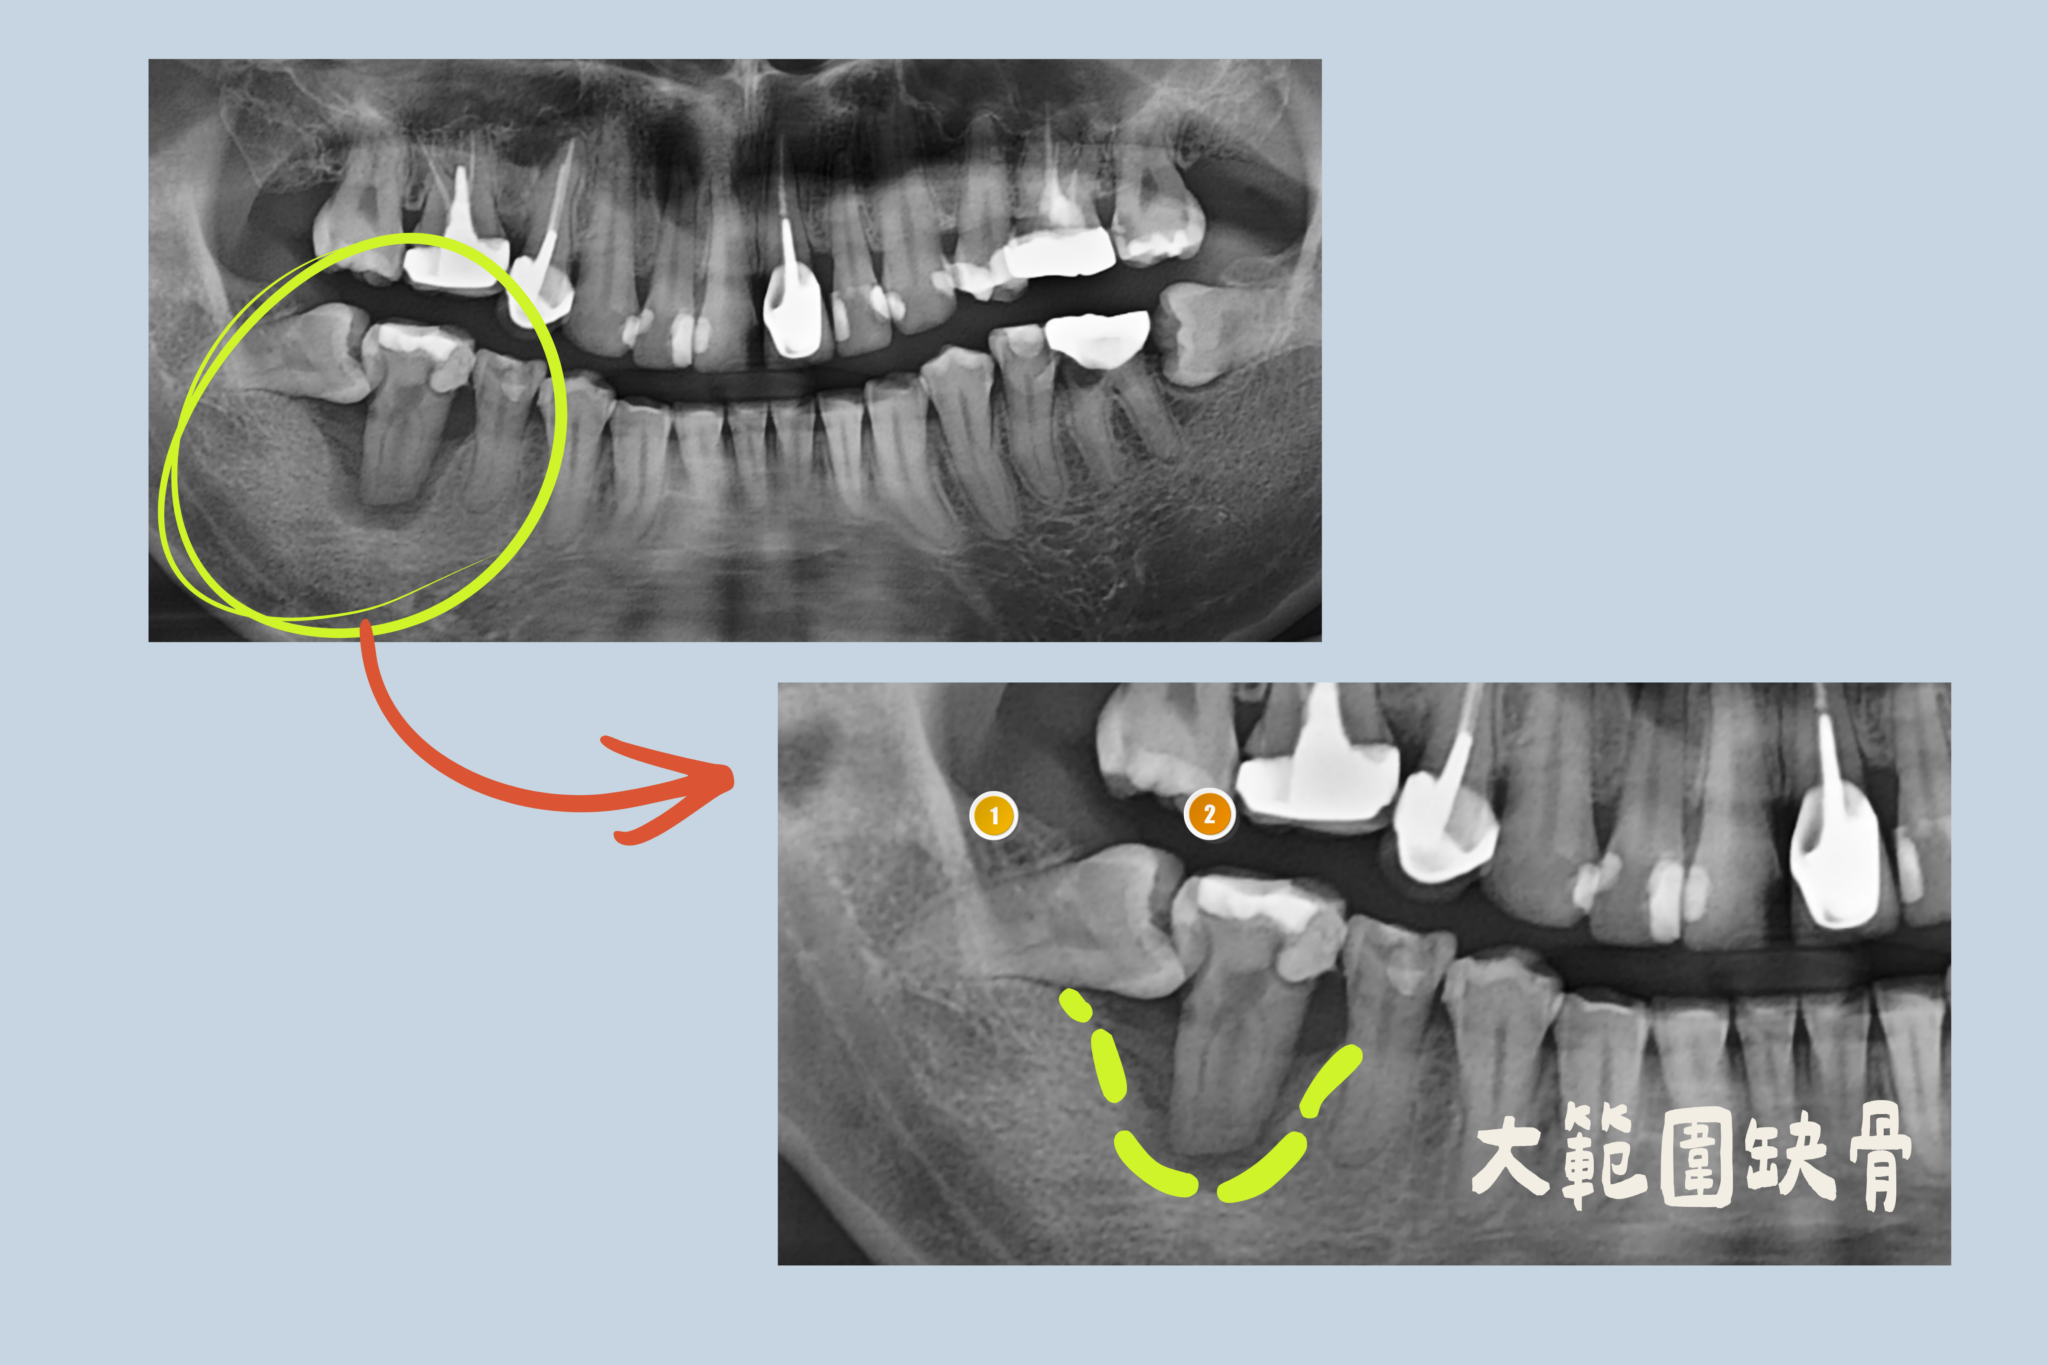

🔹 治療背景

患者因第二大臼齒長期蛀牙未處理,導致細菌感染範圍擴大,造成齒槽骨嚴重缺損,牙齒已出現明顯鬆動情形,需評估拔除。經醫師檢查後,同時發現該區域合併水平智齒問題,若僅單純拔牙,未來齒槽骨條件恐進一步惡化,影響後續植牙穩定性。

🔹 醫師評估與治療方式

郭東溫院長評估後,決定一次性處理水平智齒與第二大臼齒,並於第二大臼齒拔除當下,同步進行齒槽脊保存術(ARP),以減少拔牙後齒槽骨快速流失的風險。

由於原本骨缺損狀況較為嚴重,醫師規劃先進行 ARP,待骨頭穩定修復後,約五個月後再進行植牙療程,以確保植牙條件與長期成功率。

大範圍缺骨arp骨頭發育|東嶼牙醫